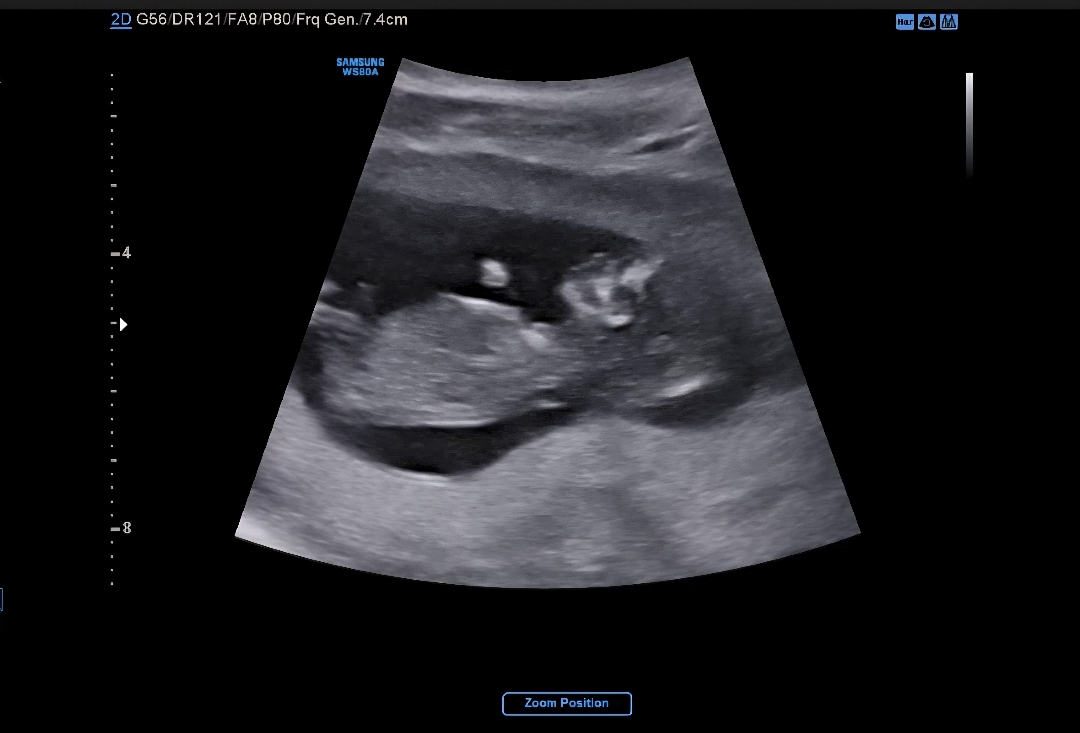

GPT는 여아라는데 저는 전혀 모르겠더라구요...ㅠㅠ 잘보시는 분들 재능을 조금만 빌려주세요..

딸 같이 보여요